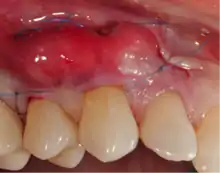

Exposure of the tooth root due to loss of keratinized tissue around the neck of a tooth is referred to as gingival recession. This can result in sensitivity or pain from the exposed tooth root surface (dentin is more permeable and soft compared to enamel and dentin is what makes up the tooth root).[7] Recession may also cause an unasthetic appearance especially if located in the anterior dentition (front teeth). While not all cases of gingival recession require surgical correction, there are various options if that is what the patient desires.[8] It should be reinforced that recession left untreated will not result in tooth loss, contrary to popular belief. Also, recession that is left untreated can be maintained and the inflammation kept at bay with proper brushing and oral hygiene technique.[5] On the other hand, if one desires to pursue corrective therapy, there are a wide variety of techniques ranging from autograft (your own tissue, usually taken from the palate), allograft (someone else's tissue, cadaver), xenograft (animal, usually porcine or bovine) or simply repositioning of the tissue native to the site.[9] The benefits of corrective therapy often result in decreased sensitivity through coverage of the root surface in addition to a gain in the keratinized tissue mentioned beforehand.

Gum grafting, also known as a gingival graft or periodontal plastic surgery, is a surgical procedure to reverse gum recession. Gum recession exposes the roots of teeth,[10] which can lead to sensitivity and put teeth at a higher risk of damage or disease[11] due to the loosening of their attachment within the gums and bones of the jaw. Should gum recession continue, bone and keratinized tissue will be at greater risk of being damaged and permanently lost around the teeth. The aim of a gum graft is to extend keratinized tissue of the gums to cover tooth roots,[12] which restores their firm placement within the jaw and prevents further damage.

A free gingival graft is a dental procedure where a small layer of tissue is removed from the palate of the patient's mouth and then relocated to the site of gum recession. It is sutured (stitched) into place and will serve to protect the exposed root as living tissue. The donor site will heal over a period of time without damage. This procedure is often used to increase the thickness of very thin gum tissue.